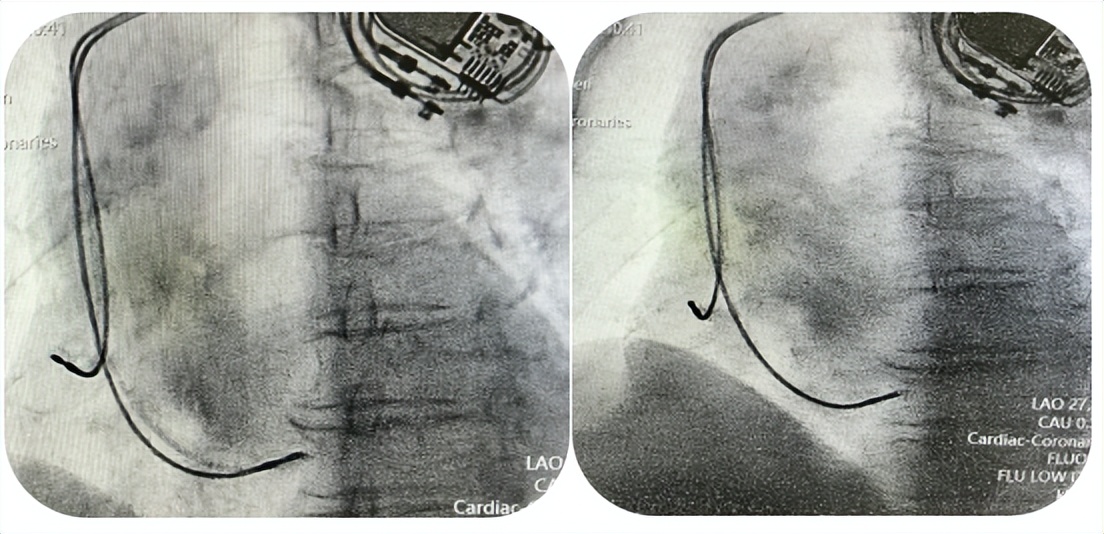

经过严谨分析,最终为蒋奶奶制定了个性化治疗方案:先植入永久双腔抗核磁起搏器,解决心脏跳动过慢的问题,再进行标准化的冠心病、心力衰竭 GDMT(指南指导的药物治疗),从多个方面控制病情。

就在同一天,安居区人民医院专家团队为她成功实施了 “经导管心脏射频消融术”,通过微创的方式,精准 “消灭” 异常的心脏电信号,让王奶奶的心脏重新恢复正常跳动节奏。